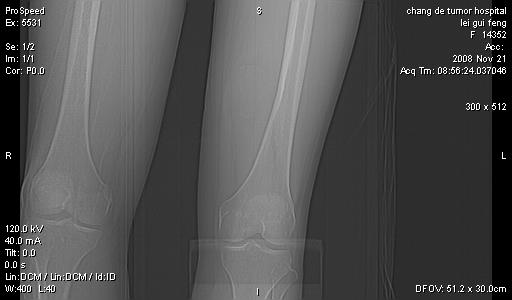

标题: CT16807:女 41 无不适 [打印本页]

标题: CT16807:女 41 无不适

“无不适” 也能插上一腿搞出个这么大的砣?最起码也应该是:自觉腿部包块,质硬或软,有或无移动,再无其它不适。

双是软组织肿瘤,病灶内多发钙化,另可见多量脂肪密度影,考虑畸胎瘤,血管瘤,不除外其他